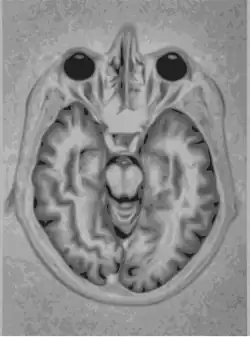

..jpg)

La imagen anterior es una imagen del cerebro. Es una prueba que permite el diagnóstico del trastorno de Parkinson. Se trata de una imagen tomográfica (SPECT).